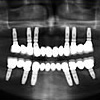

La implantología, es sin duda alguna la rama de la odontología con avances y predictabilidad más impactante hoy en día. Solo con el hecho de explorar posibilidades protesicas que eliminen el uso de "placas" o prótesis ...

Leer más